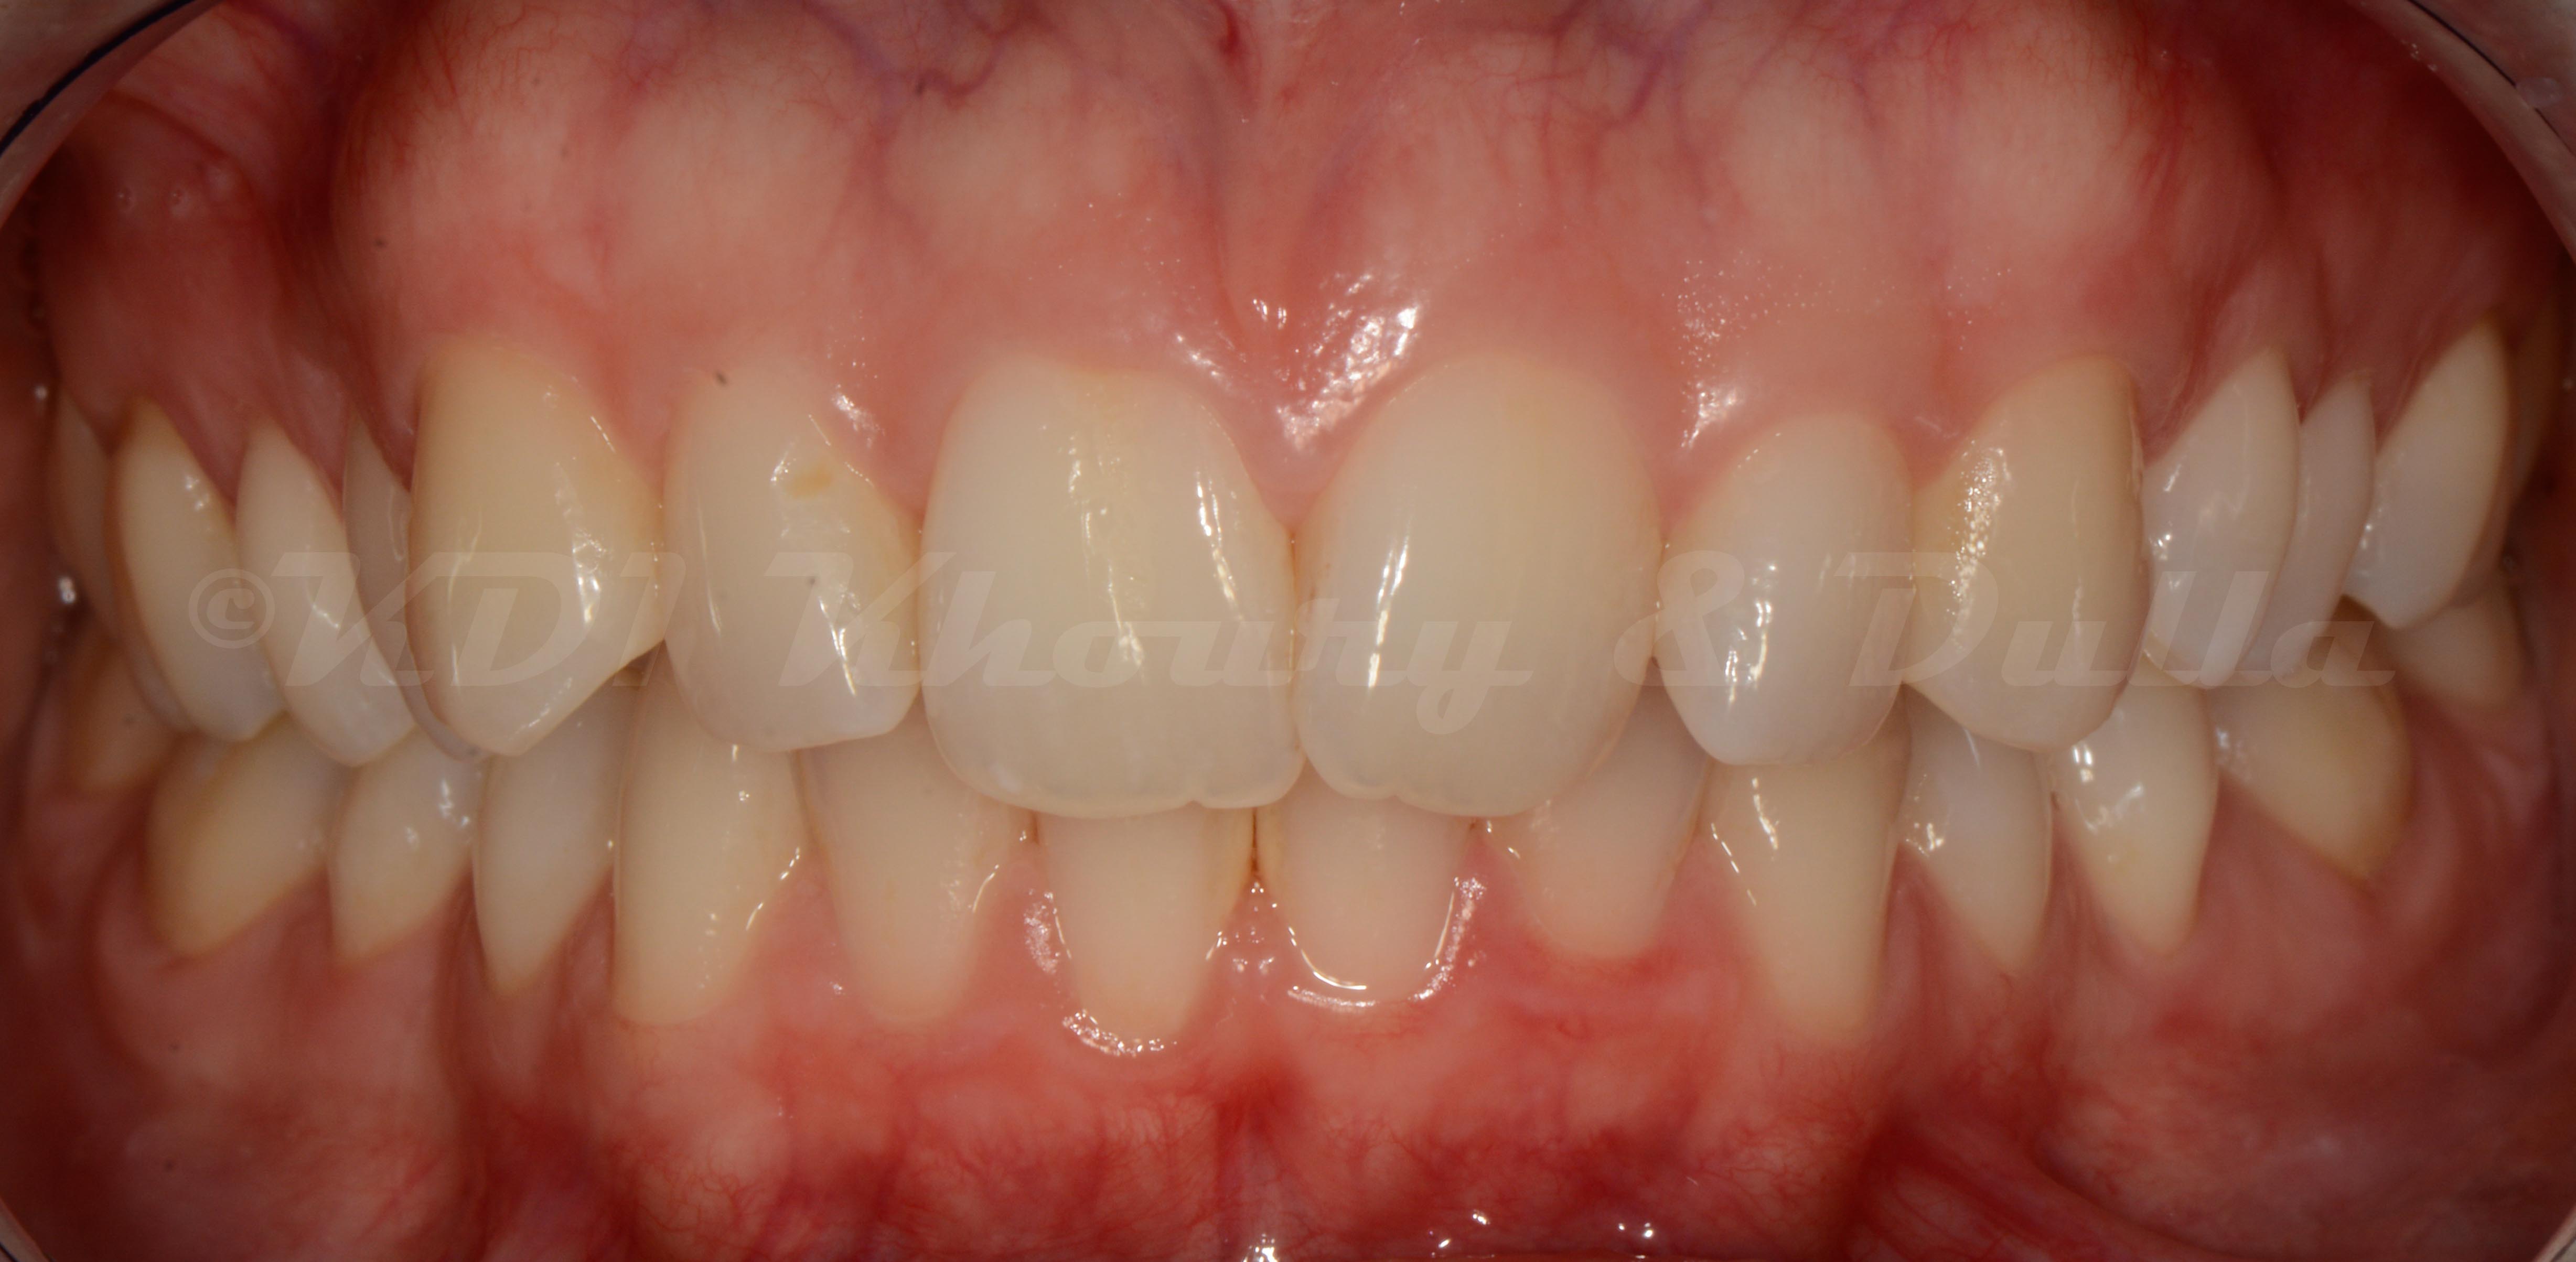

Cas #1 – Traitement avec des bagues, deuxièmes prémolaires et dent de sagesse supérieures ectopiques.